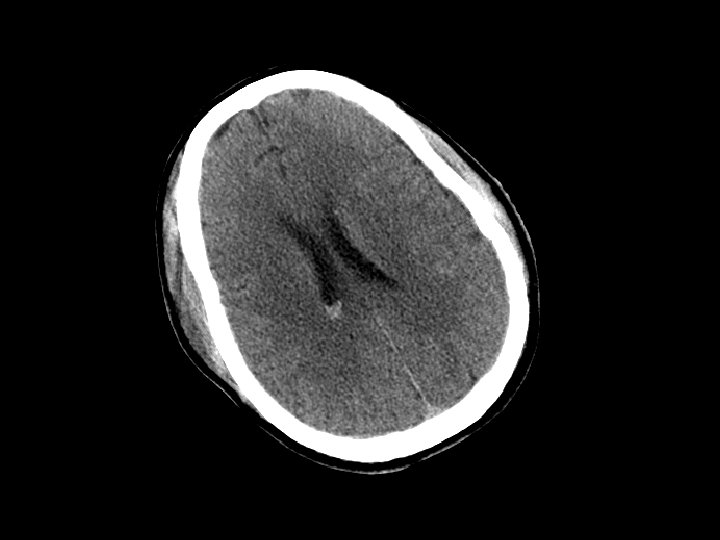

Subdural Hematoma (SDH) • Hemorrhage between the dura and the brain – More common than EDH – 30% of patients with TBI have a SDH • CT: Crescent shaped area of blood • Can be acute, subacute or chronic – Subacute or chronic presents days/weeks after injury

Subdural Hematoma (SDH) • Elderly at risk (less severe mechanisms) – Brain shrinks with age resulting in stretching of the bridging veins in the subdural space • May gradually enlarge (slower than EDH) • Surgical drainage for lesions resulting in masse effect and shift